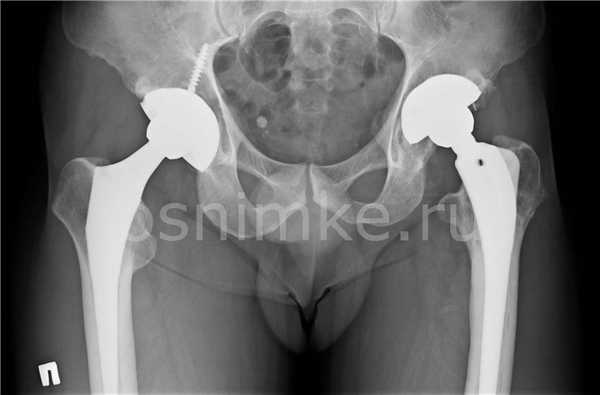

Эндопротезирование тазобедренного сустава

Рентгенограмма как метод исследования рассчитана на визуализацию костных структур. При диагностике хорошо просматриваются:

- Кости таза. Видны анатомические дефекты, переломы, трещины, асимметрия.

- Сустав. Выявляют вывихи, подвывихи, расширение суставной щели, сужение или сращение с формированием анкилозов.

- Головка бедренной кости. Просматривается вертел, шейка бедра, выявляются трещины, переломы, аномалии развития и строения, остеомиелитные и остеопорозные изменения.